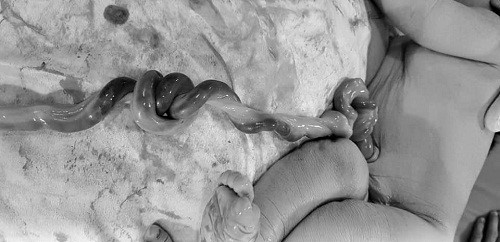

Thông tin từ Bệnh viện Từ Dũ cho biết, các bác sĩ vừa đỡ đẻ thành công cho sản phụ 32 tuổi, sinh con đầu lòng. Em bé chào đời trong sự “thót tim” của các bác sĩ vì nút thắt đôi ở dây rốn.

Đây là trường hợp tương đối hiếm gặp và ít nhiều tiềm ẩn những nguy hiểm. Theo các bác sĩ, dây rốn trung bình dài 55-100 cm. Dây rốn dài là một trong những yếu tố làm tăng nguy cơ thai nhi bị dây rốn thắt nút. Các yếu tố làm gia tăng tỉ lệ dây rốn thắt nút là thai phụ lớn tuổi, thai nhi là bé trai, trọng lượng thai nhỏ, các bé hay hoạt động, đa ối, mang thai lần thứ hai trở lên, đặc biệt đa thai chỉ có 1 túi ối. Dây rốn thắt nút được hình thành vào giai đoạn đầu của thai kỳ, khoảng từ 9-12 tuần, khi bé còn nhỏ và còn nhiều không gian để di chuyển.